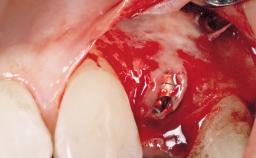

A 29-year-old female patient presented for treatment to replace the upper left central incisor tooth with an implant- supported restoration. The tooth had been intermittently symptomatic for the previous 12 months. The tooth had originally suffered trauma about 15 years previously. Several endodontic treatments had been performed, including an apicectomy procedure to retain the tooth. The patient was healthy and a non-smoker. She had reasonable expectations in regard to esthetic outcomes and the risk of marginal tissue recession following treatment. At medium smile, the gingival margins of the upper teeth were visible, with a display of 3 to 4 mm of the gingival margins. Gingival recession of tooth 21 and a discrepancy in the gingival levels between teeth 11 and 21 was observable during normal speech and smile.

Type of Implants One-Piece

Placement Protocol Immediate implant placement

Tooth Site Maxillary incisor or canine

Socket Morphology Single-root socket